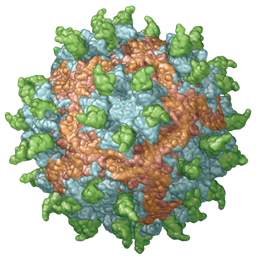

If "a picture paints a thousand words" and using visuals with text increases retention, then Precision Graphics has immeasurably enhanced

the art and science of learning. Sneak a peek under the covers of textbook illustration and

design with Precision Graphics' Jan Troutt (Vice President of Publishing Services) and Heidi Richter (Certified

Medical Illustrator and Senior Illustrator) as they highlight the successes and challenges that they've faced in an ever-changing world of illustration, design and animation.

If "a picture paints a thousand words" and using visuals with text increases retention, then Precision Graphics has immeasurably enhanced

the art and science of learning. Sneak a peek under the covers of textbook illustration and

design with Precision Graphics' Jan Troutt (Vice President of Publishing Services) and Heidi Richter (Certified

Medical Illustrator and Senior Illustrator) as they highlight the successes and challenges that they've faced in an ever-changing world of illustration, design and animation.

Founded in 1977 by Jeff Mellander, Precision Graphics is the largest educational textbook illustration

studio in the United States today. Jan Troutt, a Precision Graphics mainstay for over 24 years, has seen the

transition from one-color line drawings to today’s highly illustrated, full-color textbooks and media projects.

Heidi Richter has melded her love of science and evolution with skills learned at the University of Toronto

Biomedical Communications program as one of the team of illustrators at Precision Graphics.

With clients that include National Geographic, Scientific American, Pearson, Howard Hughes Medical Institute,

The World Bank, Precision Graphics' client list includes all the major textbook publishers as well as high-tech

corporations. Join us as Jan and Heidi show how Precision Graphics is leading the transition from the traditional static book to highly interactive digital learning.